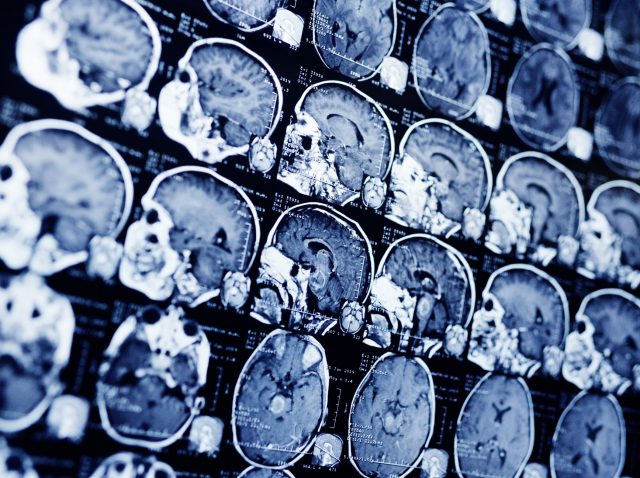

Nueva esperanza para los niños con tumores cerebrales

Tumores cerebrales infantiles La medicina de precisión, en la que el diagnóstico y los tratamientos se adaptan a las susceptibilidades genéticas de cada tipo de cáncer, puede desempeñar un papel importante en el tratamiento de los niños con tumores cerebrales, según sugiere un estudio realizado por investigadores del Dana-Farber/Boston Children’s Cancer...

Las células inyectadas en el cerebro ayudan a un hombre a combatir un cáncer mortal

Un hombre con un cáncer cerebral mortal que se había extendido a la columna vertebral vio cómo sus tumores se reducían y, durante un tiempo, desaparecían por completo tras someterse a un novedoso tratamiento destinado a ayudar a su sistema inmunológico a combatir la enfermedad, otra primicia en este prometedor campo...